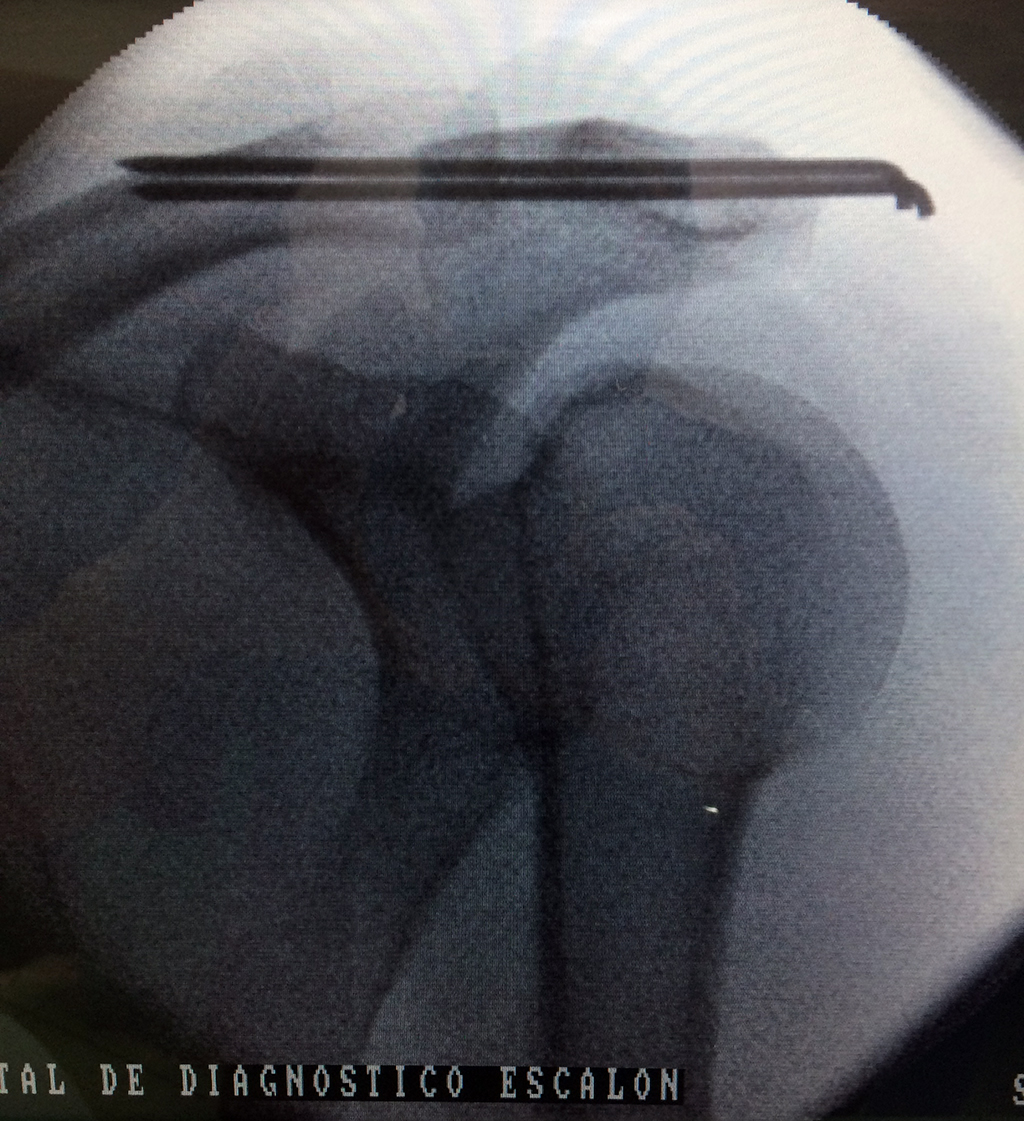

Clavicula 1

Detail Download